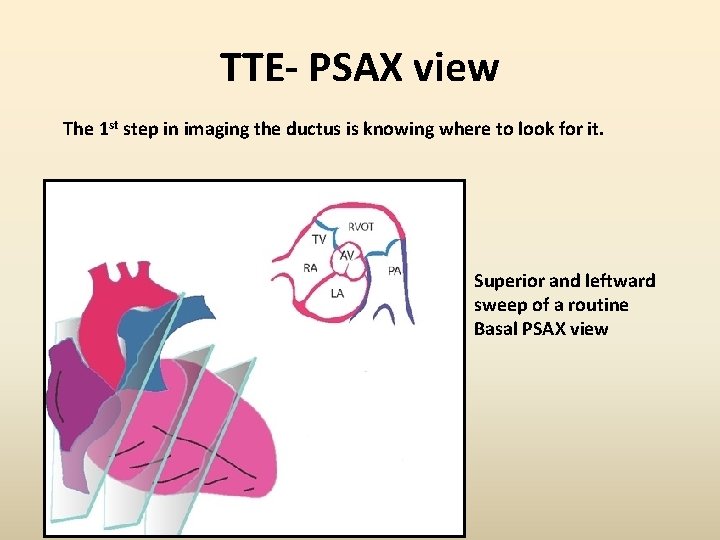

TTE- PSAX view The 1 st step in imaging the ductus is knowing where to look for it. Superior and leftward sweep of a routine Basal PSAX view

TTE-PSAX view for PDA

1. Three-legged pant view -high left PSAX view A large PDA shunting L to R is often easily visualized However smaller PDA required help of Colour Doppler